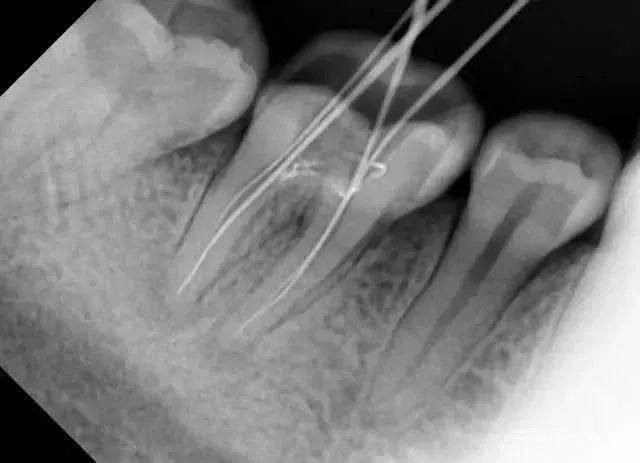

暗的部位说明龋齿已经非常严重了!

龋坏接近牙髓了